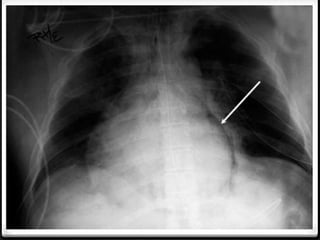

Tension pneumothoraks

hidropneumo

pericardium